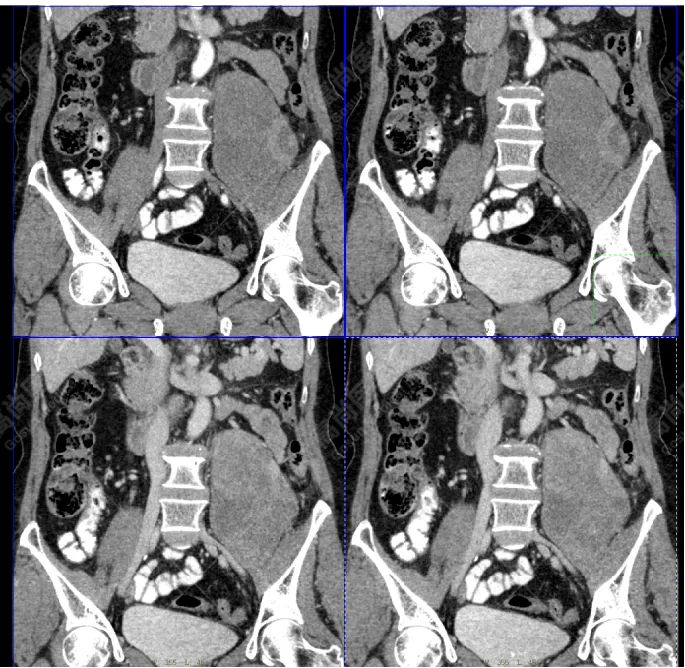

影像所见:左腹膜后间隙(原术区)见一长椭圆形软组织密度肿块影,范围约 8.0 cm×6.6 cm×15.8 cm,CT 值 30 Hu,FDG 高摄取,SUVmax5.0,考虑肿瘤复发,侵犯相邻左侧输尿管、腰大肌、后腹壁。

增强扫描肿瘤不均性中度强化,动、静脉期 CT 值:41 Hu、72 Hu(平扫 CT 值 30 Hu)。